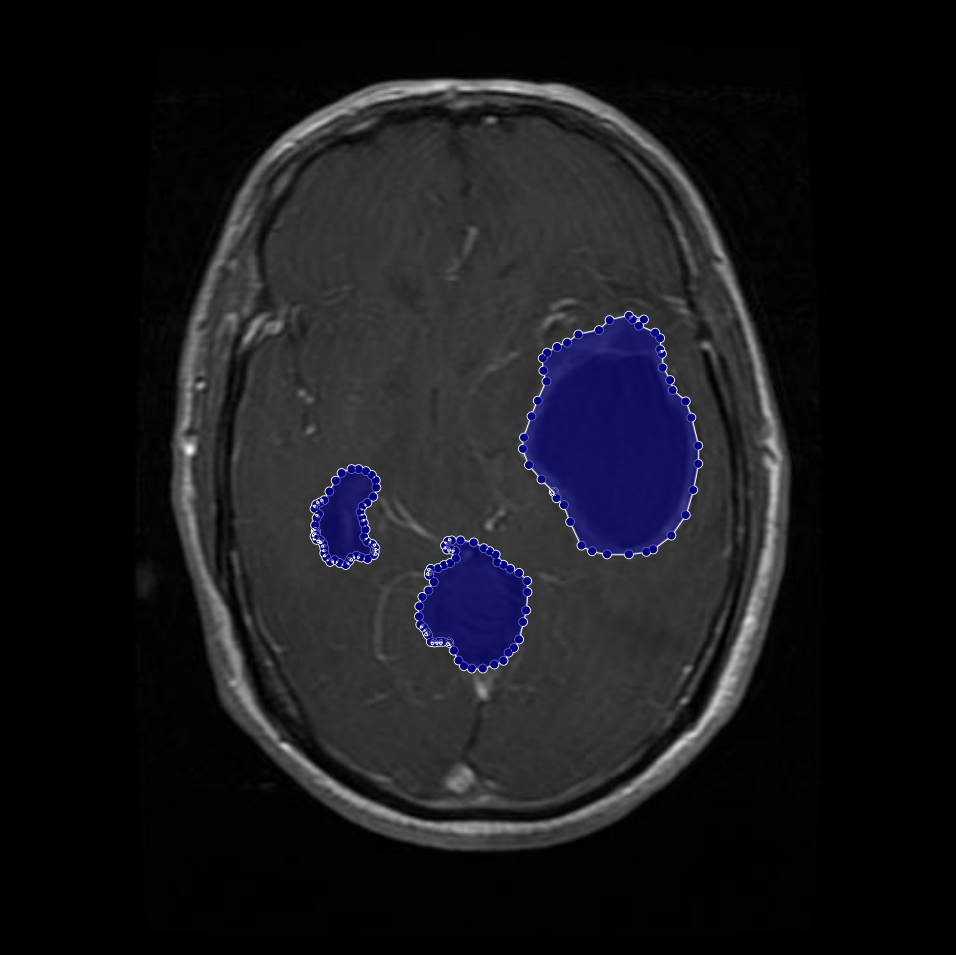

Figure 1: Samples of Glioma segmentation across different imaging planes

Glioma: Gliomas are irregularly shaped and often infiltrate surrounding tissues, presenting significant challenges for precise boundary definition. These complexities require robust segmentation techniques to capture their variable morphology. As shown in Figure 1, gliomas exhibit irregular and diffuse growth patterns, which are highlighted through annotated tumor masks.